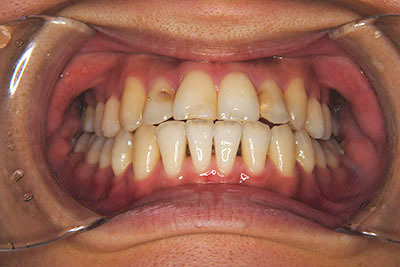

おとなの方でも矯正治療をあきらめないでください!

矯正歯科治療は子供の頃だけしかできない……

子供の頃に比べ大人になったら治療期間がすごく長い……

というようなイメージをお持ちではありませんか?

子供の頃に矯正治療を行う方が治療期間が短く済むというのは、確かですが、矯正治療は患者様の意識も重要です。

いくら歯が動き易くとも、本人がやる気でなければ効果は出ませんし、むし歯発生のリスクも高まります。おとなの方は顎の成長が終わっているため、治療の計画が立てやすいとも言えます。「もう大人だから…」とあきらめず、一度ご相談ください。

本格矯正治療の詳しい説明は小児矯正治療/本格矯正治療ページを御覧ください。